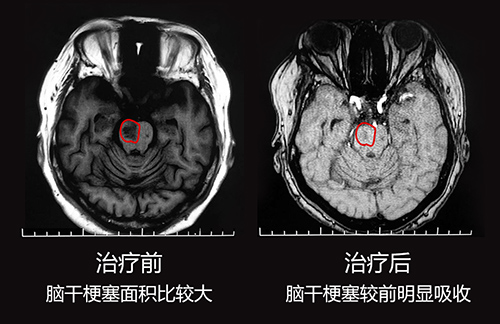

9月19錢(qián)阿姨在老伴和兒子的陪伴下就診于藍(lán)十字腦科醫(yī)院。神經(jīng)內(nèi)科特需專(zhuān)家王玉霞主任詳細(xì)了解錢(qián)阿姨的病癥和治療情況后,完善相關(guān)檢查,進(jìn)行了頭顱MRI平掃+DWI+MRA,檢查結(jié)果:1、患者腦干梗塞(急性期);2、雙側(cè)大腦半球白質(zhì)多發(fā)腔梗;3、腦白灰疏松;4、MRA腦動(dòng)脈硬化。

檢查結(jié)果顯示,錢(qián)阿姨目前腦干梗塞情況還是比較嚴(yán)重的,王玉霞主任決定先對(duì)其進(jìn)行藥物治療,通過(guò)藥物治療可以活血通絡(luò),擴(kuò)張血管,改善微循環(huán),控制和縮小其腦干梗塞面積,之后再結(jié)合中醫(yī)治療和康復(fù)治療。經(jīng)過(guò)一周有效的治療后,錢(qián)阿姨腦干梗死情況比之前明顯好轉(zhuǎn),病情基本穩(wěn)定,王玉霞主任告訴錢(qián)阿姨接下來(lái)主要就是康復(fù)治療問(wèn)題。